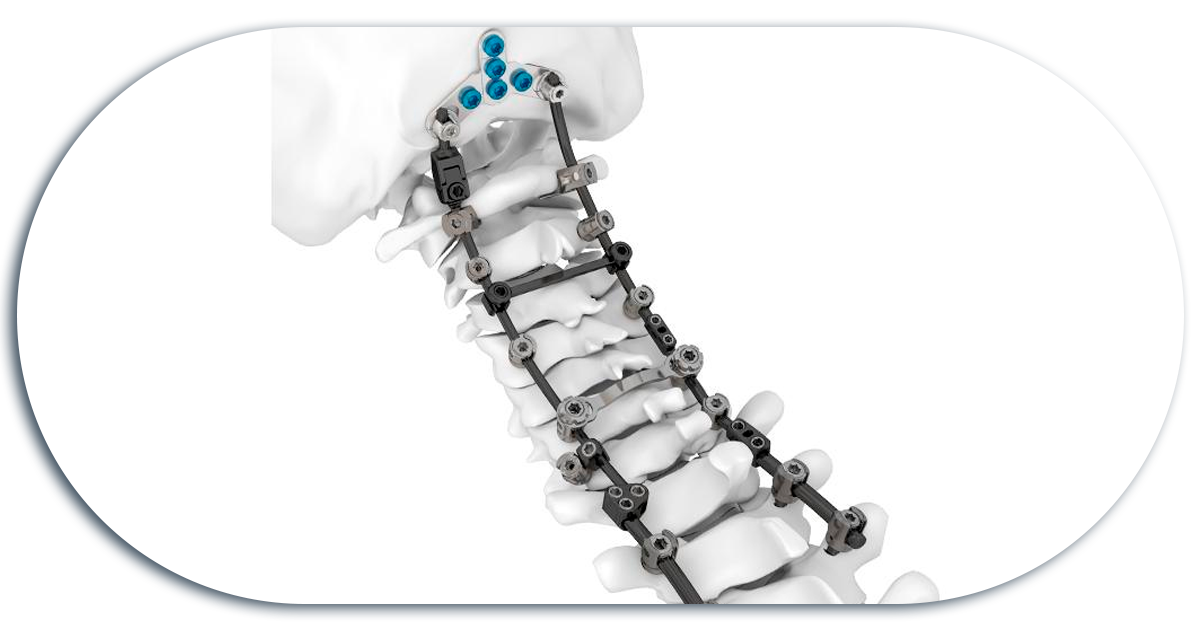

Posterior Cervical Fixation

Screws are used, which are placed in bony structures called facets, and these screws are then fixed to each other with longitudinal bars.